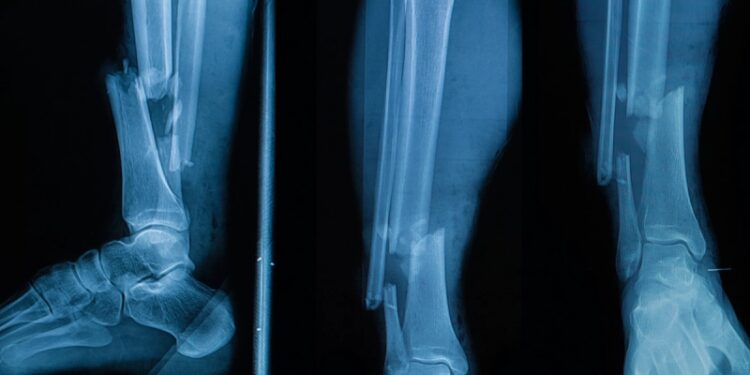

Группа ученых из США и Южной Кореи провела первые успешные испытания новой технологии по созданию костных имплантов непосредственно в месте повреждения костей. Они модернизировали клеевой пистолет, чтобы наносить специальный состав в нужную область в требуемых количествах. Он не заменяет собой кость, но позволяет устранить повреждения на время, пока костная ткань не разрастется и не заполнит этот участок.

Главное преимущество технологии в возможности отказаться от громоздких конструкций для фиксации обломков костей, а также сократить время лечения повреждений. Имплант формируется хирургом прямо во время операции, в организм не добавляется ничего лишнего, кроме небольшого объема вещества для замещения поврежденных частей костей. Процесс занимает считанные минуты, затем в течение 12 недель формируется новая структура, когда композит становится каркасом, на котором нарастает новая костная масса.